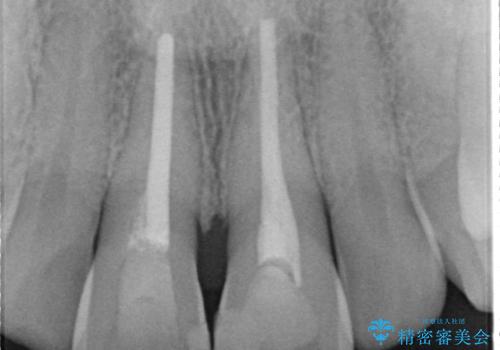

セラミッククラウンで前歯の変色を改善

- 前歯の変色が気になるというご相談をいただき、セラミッククラウンによる治療を行いました。

セラミッククラウンによって前歯の変色が改善され、また歯の形も希望の形態へ修正しました。